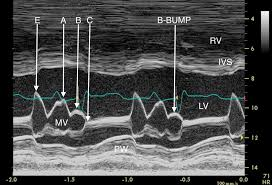

Delayed mitral valve closure due to elevated EDP

Dilated cardiomyopathy

What does the b-bump represent on m-mode?

What condition is it seen in?